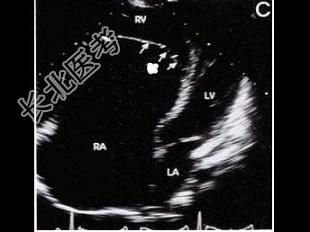

- 单项选择题该病例最可能的诊断是(   )

A、三尖瓣下移

B、异位腱索

C、室间隔缺损

D、右室双腔

E、三尖瓣缺如